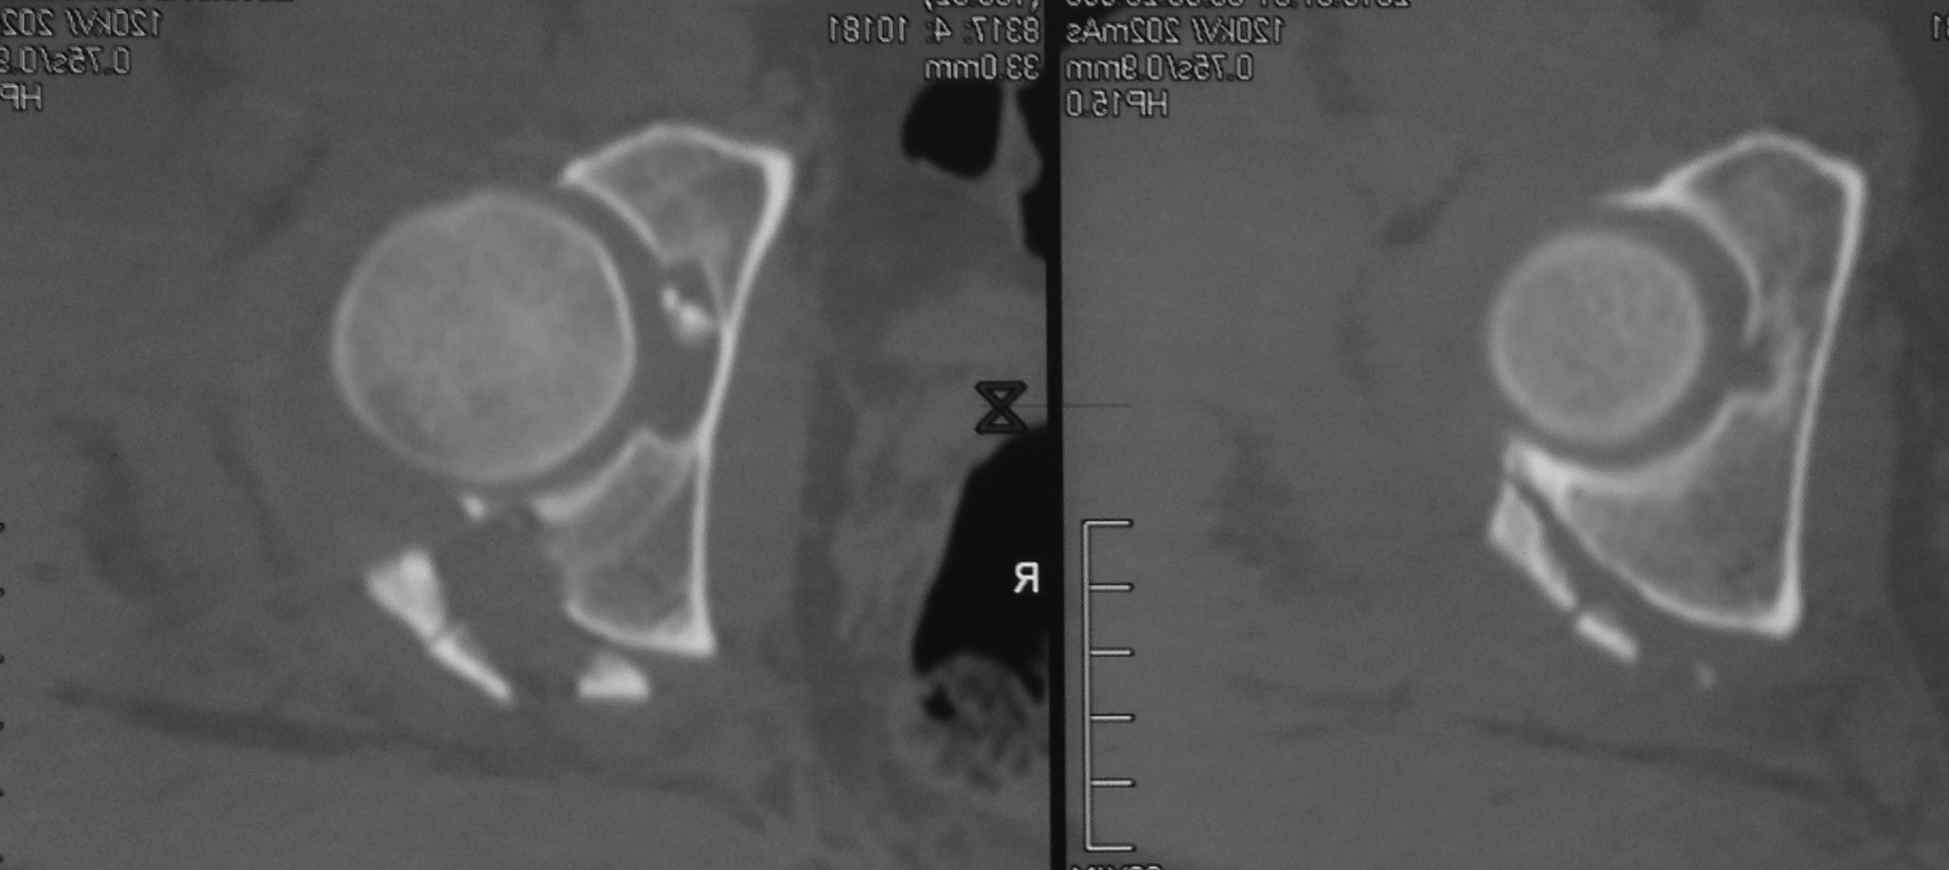

Серия КТ сканов в аппарате

Голень-41-С3.1 - полный внутрисуставной и метафизарный оскольчатый перелом с доминантным повреждением наружного мыщелка, с импрессией центральной части плато. Первичная тактика полный респект по АО и ОТА. на фоне лигаметотаксиса выполнено КТ, которое четко детализирует повреждение и определяет дальнейшую тактику.

Основная проблема не бугристость, а внутрисуставное повреждение латерального мыщелка с импрессией центральной части. С большей вероятностью, есть паракапсуллярное продольное повреждение наружного мениска.